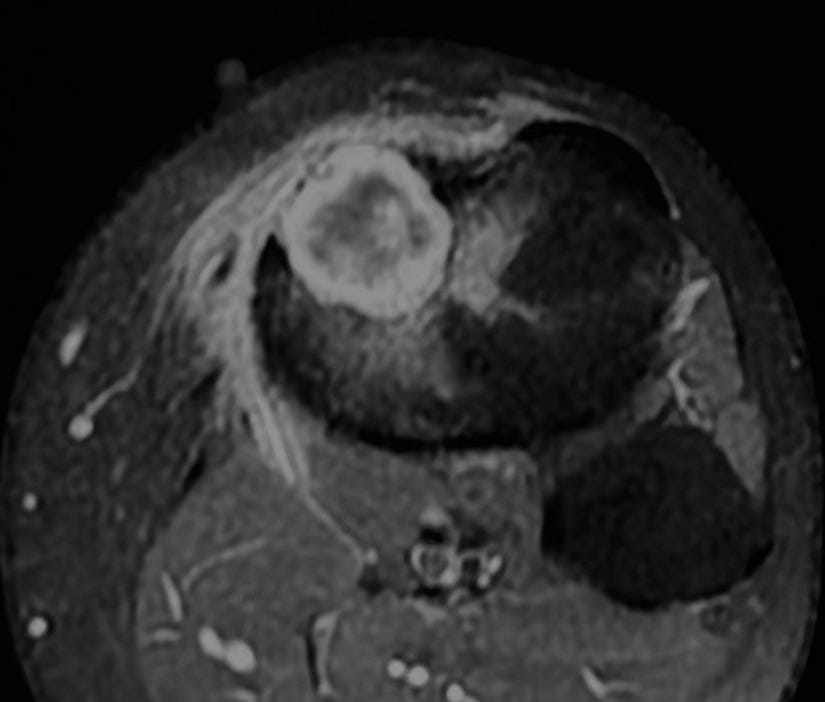

MRI shows marrow edema - this is now a “benign aggressive” lesion.

The lesion is partly T2 dark and shows a lamellated pattern of enhancement and is eccentric juxtamedullary.

A biopsy was done.

The findings are characteristic of chondromyxoid fibroma.